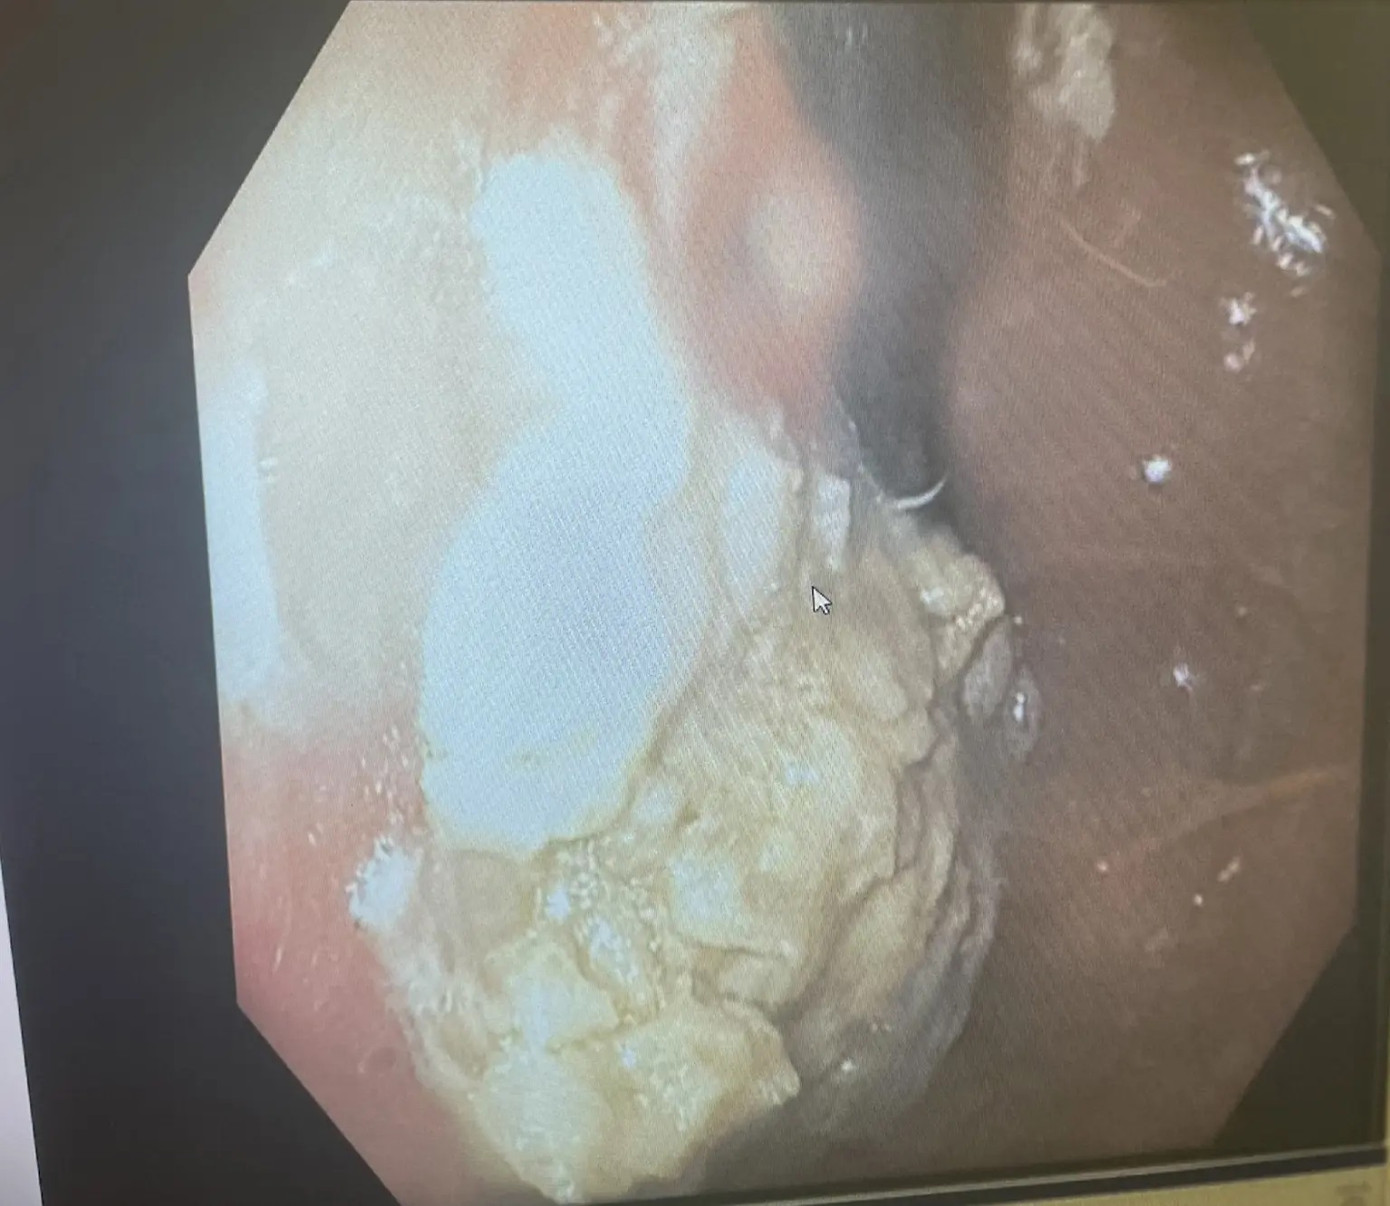

| Khối kẹo cao su được nhìn thấy trên camera trong bụng cậu bé |

Các bác sĩ đã loại bỏ kẹo cao su bằng cách đặt một ống nội soi thực quản, xuống cổ họng của cậu bé và sử dụng kẹp để gắp phần tích tụ.